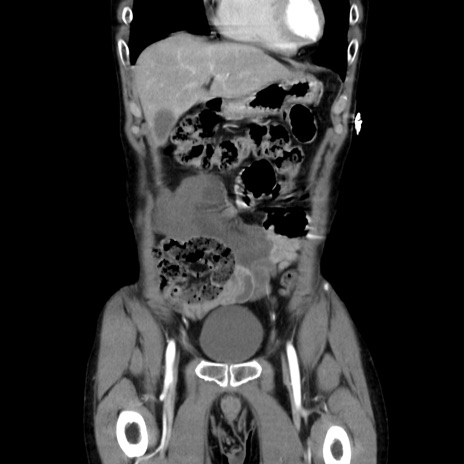

症例37(冠状断像)

【症例】40歳代 男性

【主訴】腹痛

【現病歴】4時間ほど前に電車に乗車中に臍部上より腹痛出現。徐々に増悪し起立困難となり、救急外来受診。生ものは数日食べていない。今朝お雑煮を食べた。

【身体所見】BT 36.8℃、BP 117/84mmHg、HR 91/min、SpO2 97%、苦悶様、腹部:臍上部広範囲圧痛あり、反跳痛±

【データ】WBC 8100、CRP 0.03